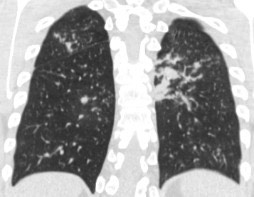

1886. Пациент 18 лет с острым миелобластным лейкозом перенес две аллогенные трансплантации гемопоэтических стволовых клеток в связи с гипофункцией трансплантата, при госпитализации с подозрением на рецидив появилась лихорадка, общая слабость, выполнена компьютерная томография грудной клетки, что соответствует